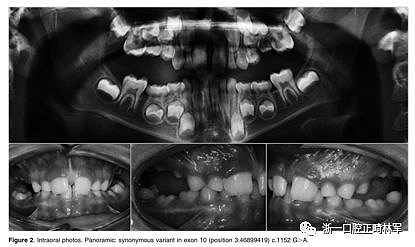

正畸文獻(xiàn)閱讀--原發(fā)性萌出失?。夯旌涎懒械呐R床和遺傳學(xué)研究

圖2.口內(nèi)照片。全景:外顯子10中的同義變體(位置3:46899419)c.1152 G>A.

在PFE的另一個(gè)孤立案例中,重新發(fā)生錯(cuò)義突變,c.64 C>T p。 先前未描述的Ala22Val在外顯子3中發(fā)現(xiàn)。這種變體發(fā)生在信號(hào)肽水平的PTH1R蛋白的胞外結(jié)構(gòu)域中,并且它確定了氨基酸的變化。但是,由于兩個(gè)氨基酸具有相同的電荷,所以該突變不被認(rèn)為是高致病性的。